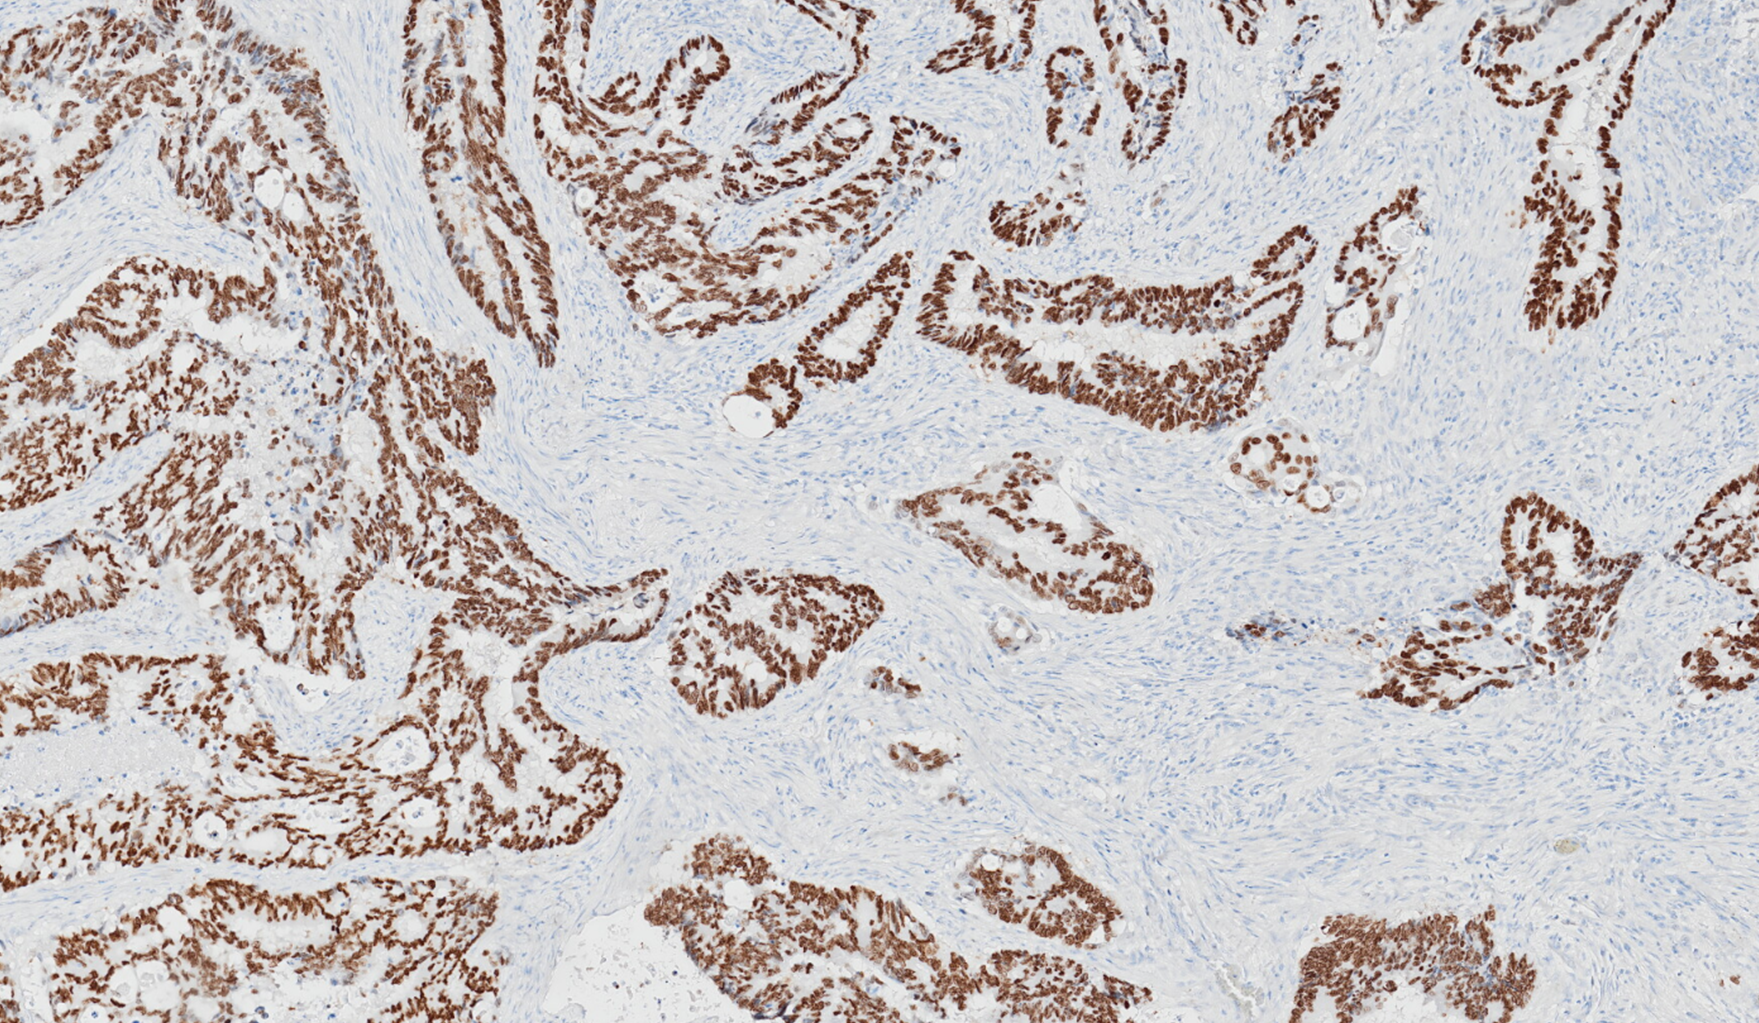

Le nouveau système utilise uniquement des anticorps à score optimal, ce qui permet aux laboratoires de générer des lames à score optimal avec des résultats plus rapides et plus rationnels.

Le Tissue-Tek Genie® est le premier et le seul véritable système de coloration avancé entièrement automatisé à accès aléatoire pour l’immunohistochimie (IHC) et l’hybridation in situ (ISH).

Optimal et unique</br>Coloration avancée